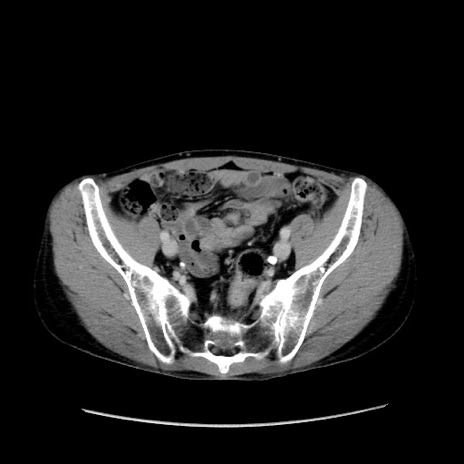

症例37(横断像)

【症例】40歳代 男性

【主訴】腹痛

【現病歴】4時間ほど前に電車に乗車中に臍部上より腹痛出現。徐々に増悪し起立困難となり、救急外来受診。生ものは数日食べていない。今朝お雑煮を食べた。

【身体所見】BT 36.8℃、BP 117/84mmHg、HR 91/min、SpO2 97%、苦悶様、腹部:臍上部広範囲圧痛あり、反跳痛±

【データ】WBC 8100、CRP 0.03